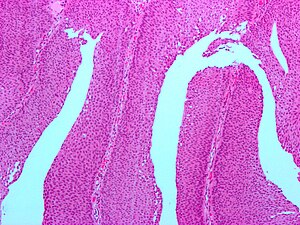

PUNLMP. H&E stain. | |

| LM | rare fused papillae, infrequent mitoses, nuclei larger than papilloma - but monotonous |

Features:[5]

- Rare fused papillae.

- Infrequent mitoses.

- Nuclei larger than papilloma - but monotonous.[6]

The sections show a papillary urothelial lesion with minimal anisonucleosis. The papillae are predominantly slender and branch. Minimal proliferative activity is present. The lesion is well demarcated in relation to the subepithelial tissue.